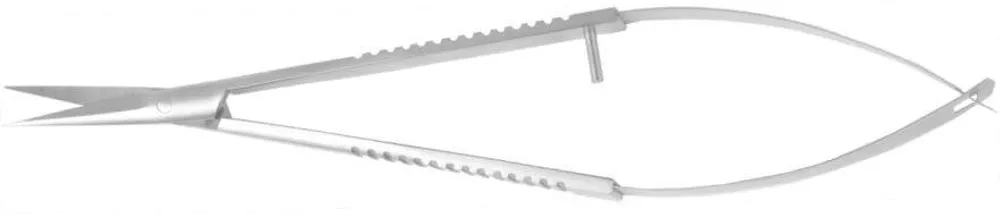

Главная / Каталог / Инструменты / Ножницы / НОЖНИЦЫ МИКРОХИРУРГИЧЕСКИЕ IRIDECTOMY SCISSORS М 103.2; М 103.3; М 103.4; М 103.7 (23)

НОЖНИЦЫ МИКРОХИРУРГИЧЕСКИЕ IRIDECTOMY SCISSORS М 103.2; М 103.3; М 103.4; М 103.7 (23)

«NOYES»

бранши плоские,

ширина бранш 7,8 мм

длина лезвия 22,5 мм

длина общая 118 мм